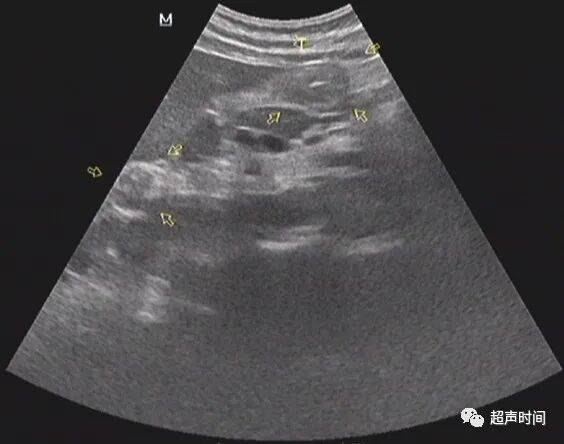

图 1

胃窦壁不规则增厚,回声减低, CDFI :其内可见高阻血流。胃窦壁僵直,探头按压长时间不蠕动。余胃壁蠕动良好。

超声提示:胃窦病变,考虑胃窦癌(建议胃镜活检及增强 CT 检查)